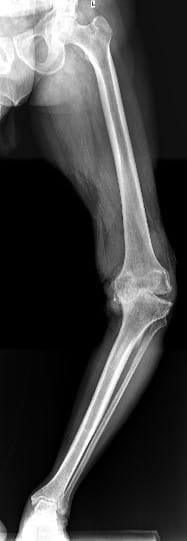

Your doctor will do clinical examination of knee joint, hip joint, spine and other joints of your body. X-rays of both knees will be performed. Occasionally, MRI of the Knee joint and few blood investigations may be required as per their underlying problem.